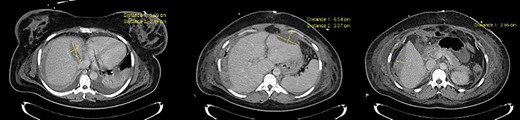

Thirty-one-year-old pregnant woman, primigravida, with history of obesity, admitted at 35 weeks of gestation due to pain in the right abdomen with 2 weeks of evolution. On admission: hemodynamically stable with tenderness on the right quadrants of the abdomen. The initial blood work only revealed thrombocytopenia (120 × 103/μl) and impaired hepatic function (AST 65 U/L, ALT 88 U/L). The patient was kept on observation, with aggravation of symptoms. Blood work showed anemia (6.9 g/dl), thrombocytopenia (113 × 103/μl) and impaired hepatic function (AST 363 U/L, ALT 399 U/L, LDH 505 U/L). The patient underwent an emergency c-section, during which an extensive hemoperitoneum was observed. It was then converted to median laparotomy in which was observed hepatic rupture of segments V, VI and VII; packing was performed and the abdomen closed. A second-look laparotomy was performed 48 hours later. Two new subcapsular hematomas were found in the left lobe, but without active hemorrhage, which led to the removal of the packing (Figs 3–5).

The patient recovered without complications and was discharged on the 13th postoperative day (Fig. 6).